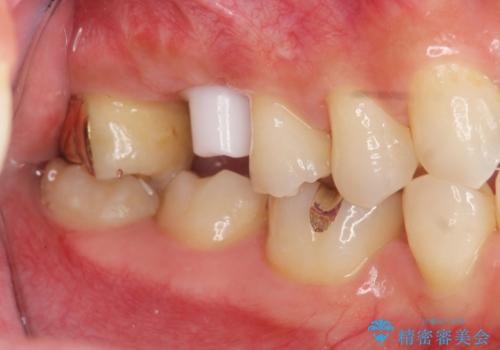

ソケットリフトを伴うインプラント補綴

治療症例の内容

- 右上の歯を喪失し機能回復を希望され来院されました。

骨量が不十分であった為、ソケットリフトを併用しインプラントによる補綴計画を立てます。

- 50万円(ストローマンインプラント・ソケットリフト・ジルコニアカスタムアバットメント・ジルコニアクラウン)費用は治療当時の料金となります